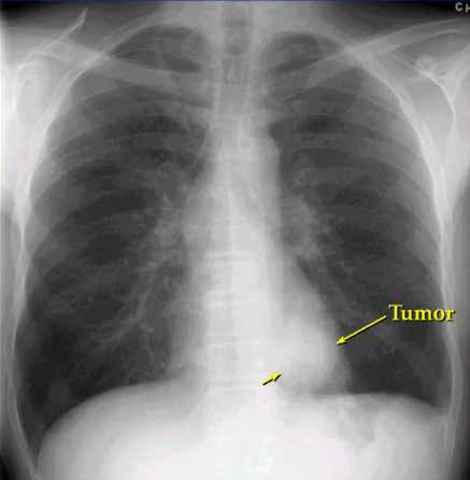

• Lung X-Ray

Lung X-Ray

X-rays reveal a tumor on Disney's left lung.

• Disney Dies

Disney Dies

Disney dies at the age of 65 to lung cancer.